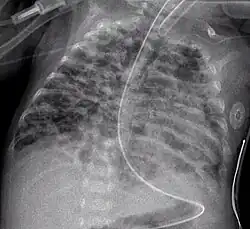

Diffuse shadowing

The differential for diffuse shadowing is very broad and can defeat even the most experienced radiologist. It is seldom possible to reach a diagnosis on the basis of the chest radiograph alone: high-resolution CT of the chest is usually required and sometimes a lung biopsy. The following features should be noted:

- type of shadowing (lines, dots or rings)

- reticular (crisscrossing lines)

- companion shadow (lines paralleling bony landmarks)

- nodular (many small dots)

- rings or cysts

- ground glass

- consolidation (diffuse opacity with air bronchograms)

- location (where is the lesion worst?)

- upper (e.g., sarcoid, tuberculosis, silicosis/pneumoconiosis, ankylosing spondylitis, Langerhans cell histiocytosis)

- lower (e.g., cryptogenic fibrosing alveolitis, connective tissue disease, asbestosis, drug reactions)

- central (e.g., pulmonary edema, alveolar proteinosis, lymphoma, Kaposi's sarcoma, PCP)

- peripheral (e.g., cryptogenic fibrosing alveolitis, connective tissue disease, chronic eosinophilic pneumonia, bronchiolitis obliterans organizing pneumonia)

- lung volume

- increased (e.g., Langerhans cell histiocytosis, lymphangioleiomyomatosis, cystic fibrosis, allergic bronchopulmonary aspergillosis)

- decreased (e.g., fibrotic lung disease, chronic sarcoidosis, chronic extrinsic allergic alveolitis)

Pleural effusions may occur with cancer, sarcoid, connective tissue diseases and lymphangioleiomyomatosis. The presence of a pleural effusion argues against pneumocystis pneumonia.

- Reticular (linear) pattern

- (sometimes called "reticulonodular" because of the appearance of nodules at the intersection of the lines, even though there are no true nodules present)

- Nodular pattern

- Cystic

-

- cryptogenic fibrosing alveolitis (late stage "honeycomb lung")

- cystic bronchiectasis

- Langerhans cell histiocytosis

- lymphangioleiomyomatosis

- Consolidation

- pneumonia

- alveolar haemorrhage

- alveolar cell carcinoma

- vasculitis